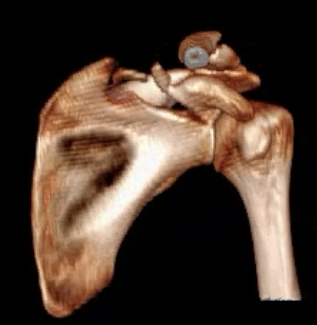

Type II: Fracture glenoid fossa that exits laterally

Definition

Transverse fracture through glenoid fossa

- inferior triangular fragment

- exits lateral border scapula